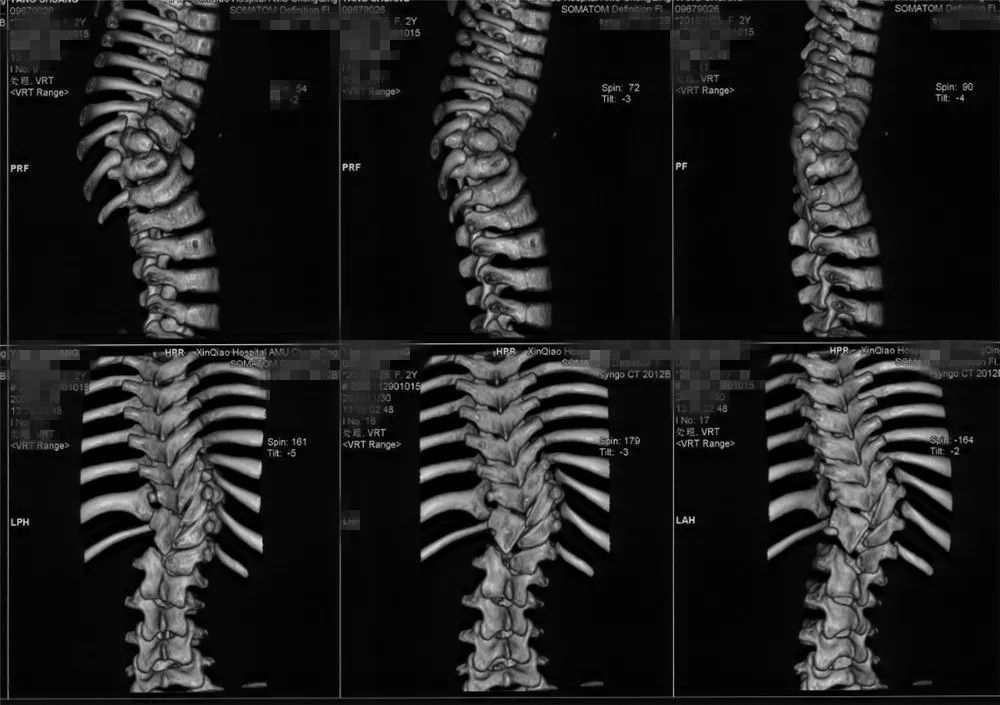

在接诊亭亭后,黄博副教授为孩子做了相关检查后发现,亭亭胸腰椎已经发生了严重的侧弯,原本正常的脊柱已变成“S”型,并且已经导致躯干的严重偏斜。黄博副教授介绍,像亭亭这样的脊柱侧弯是因为先天性的椎体发育异常造成的。有别于其他到青春期发育才发生明显形变的患者,亭亭发病非常早,通过与三个月前的X光检查对比,发现脊柱畸形明显进展,侧弯的角度已由此前的52°快速加剧到73°,如果不及时治疗,会对孩子生理和心理造成各种影响,严重的还可能导致心肺功能受损甚至死亡。

04|3D打印技术

为更精准完成侧弯矫正手术中螺钉的植入,畸形椎体的切除,黄博副教授团队还利用骨科数字化、智能化平台,术前根据CT影像1比1制作胸腰段畸形区域的3D打印模型,一方面组织医疗团队利用模型与拟植入螺钉进行实物比对,提前计算拟植入螺钉的方向、角度,预计使用螺钉的长度和直径;另一方面,利用模型预先设计术中截骨矫形方案,通过多管齐下的措施,进一步提高了手术的精准性和安全性。